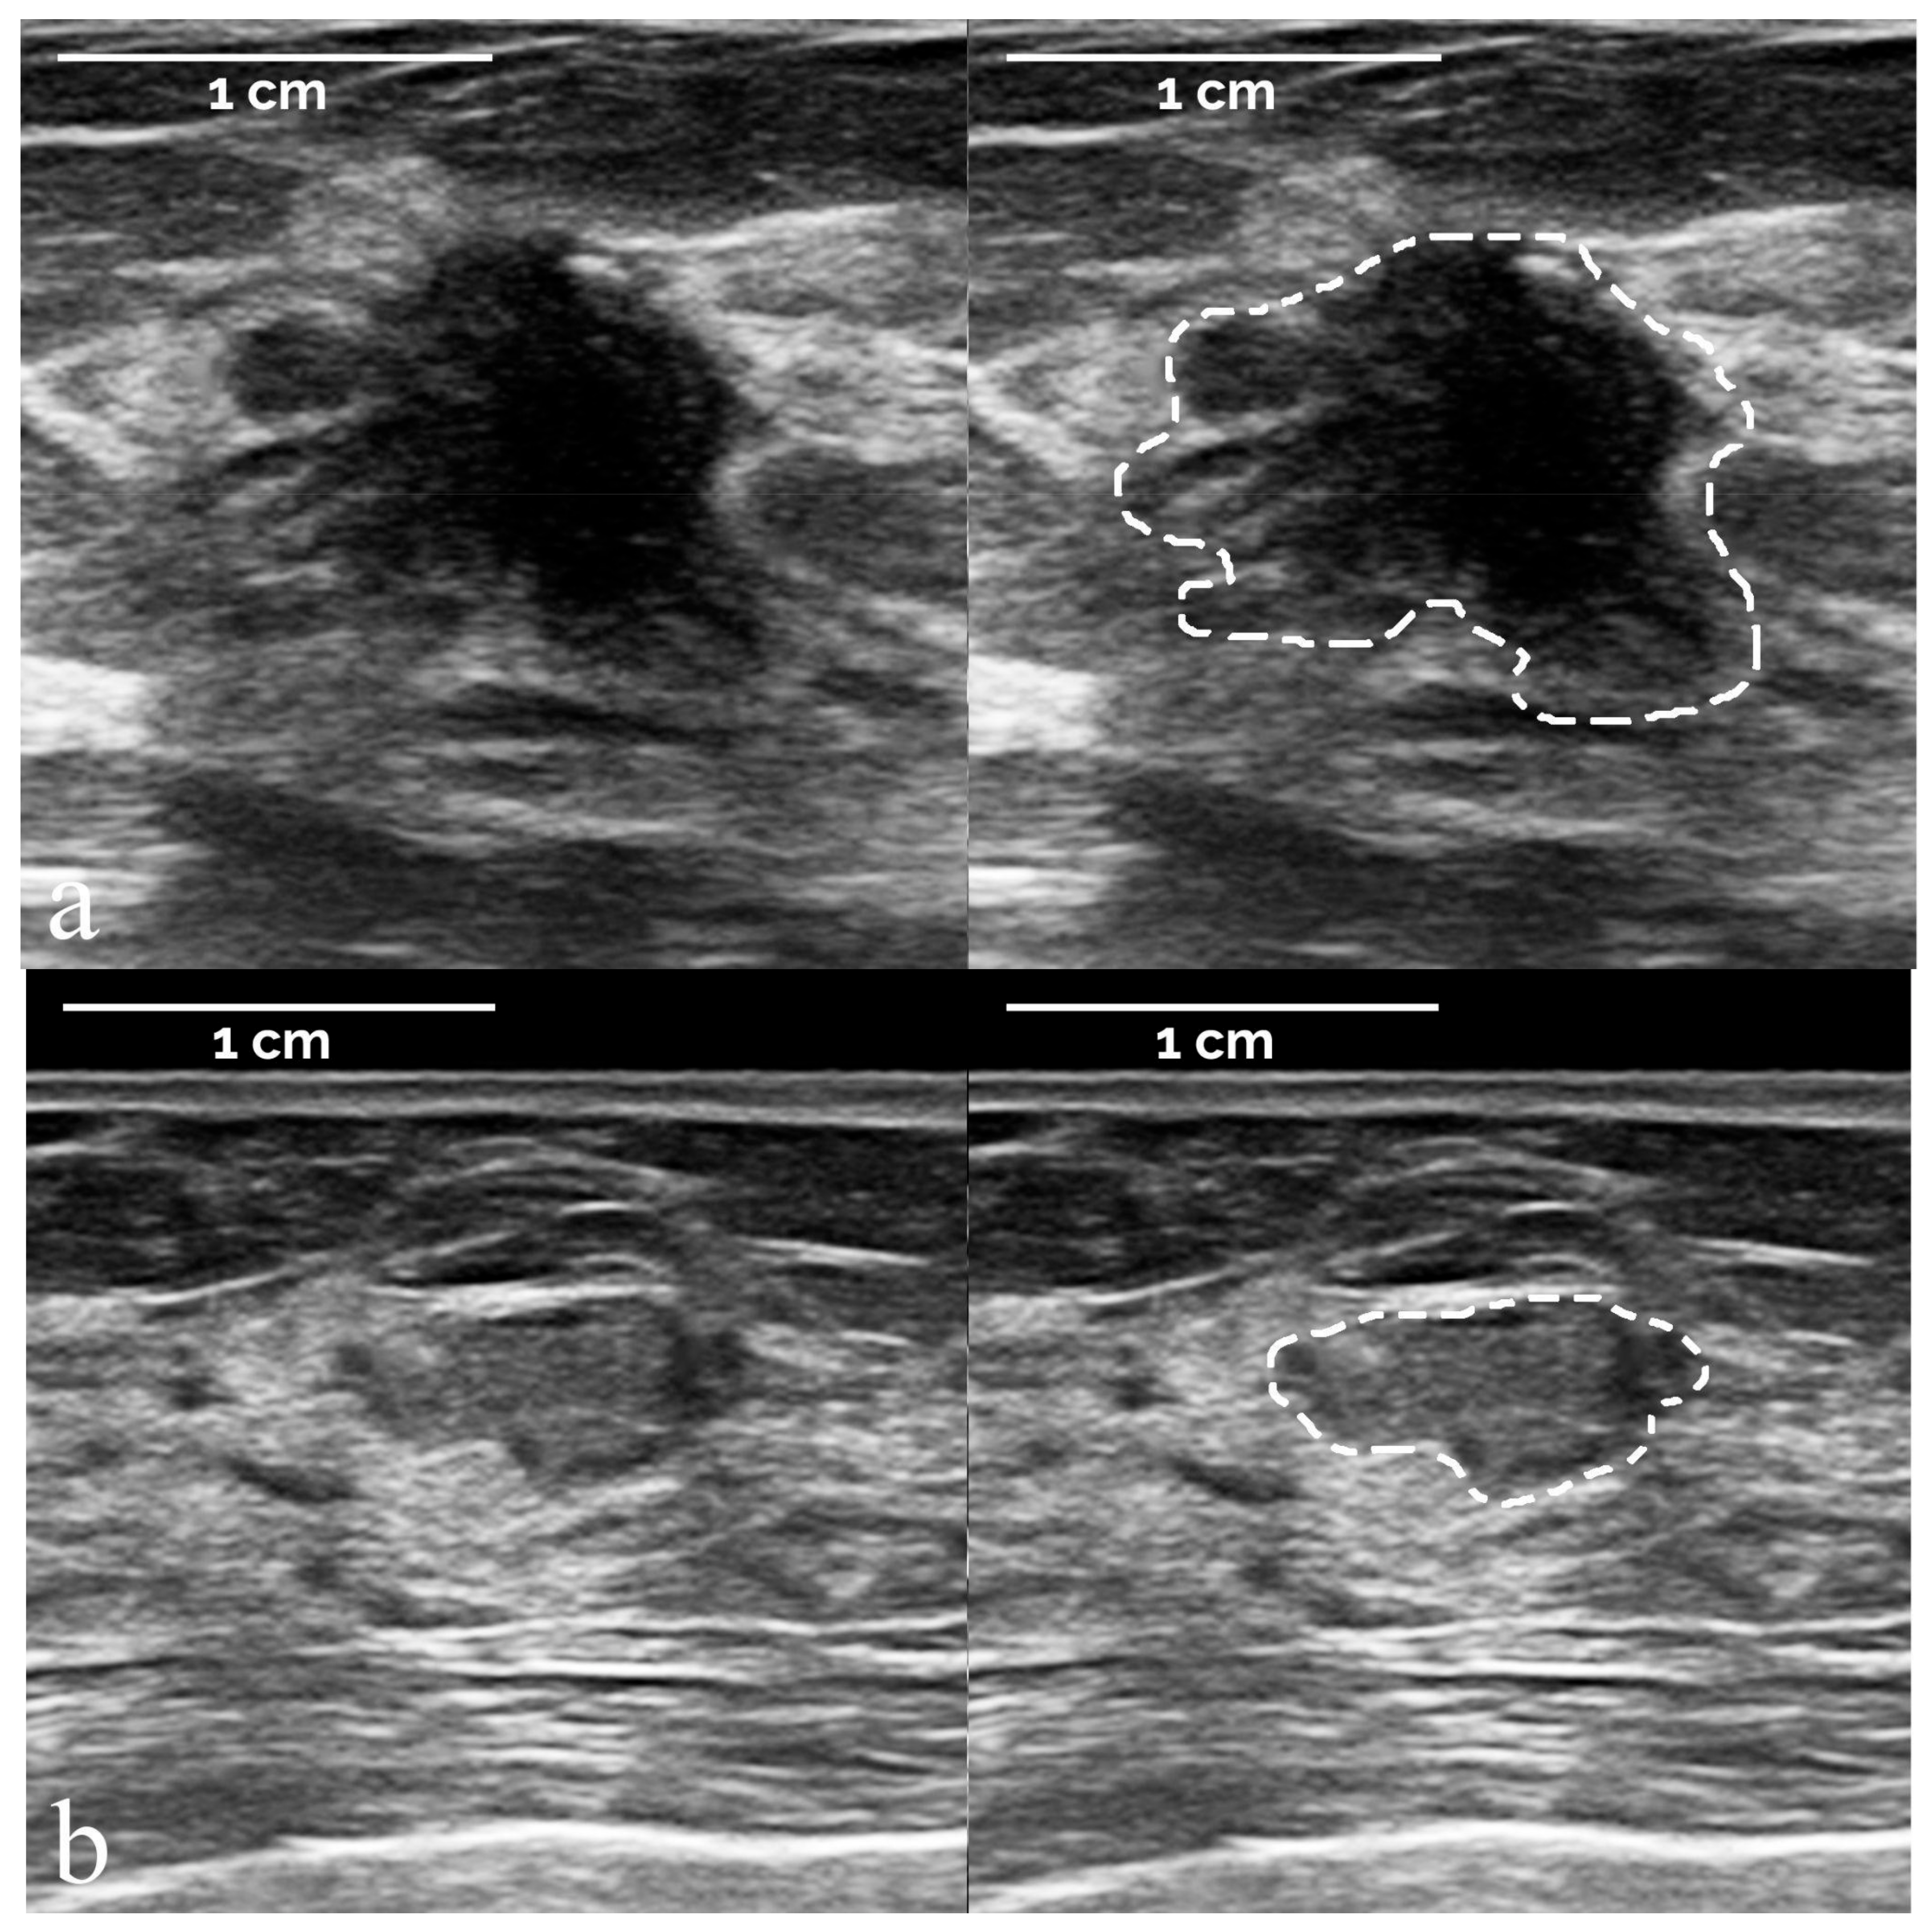

- The segmentation of suspicious masses on all 821 images was performed manually by a board-certified radiologist with 34 years of experience in breast imaging, using the TRACE4 segmentation tool. The same radiologist (at a time distance of 8 weeks) and a second board-certified radiologist with 7 years of experience independently segmented the masses on a random subsample of 50 images from the training dataset, fully blinded to histopathology and other segmentations.